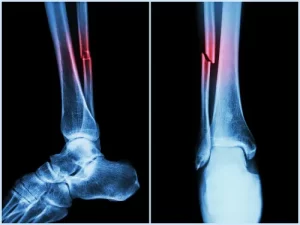

Fraturas complexas

Hoje em dia, as fraturas deslocadas ou complexas são difíceis de tratar. Muitas das vezes exigem cirurgias e isso demora em um longo tempo de recuperação do paciente.

E o doente normalmente precisa permanecer com a parte do corpo que foi quebrada imobilizada até que a cicatrização completa ocorra.